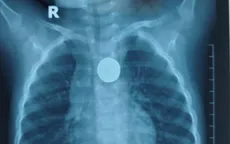

Bé trai 32 tháng nuốt pin cúc áo, bị loét thực quản

VTV.vn - Bệnh viện Nhi Hải Phòng vừa cấp cứu bé trai 32 tháng nuốt pin cúc áo. Dù được phát hiện và đưa đến viện trong 1 giờ, trẻ vẫn bị loét lớn thực quản do pin ăn mòn rất nhanh.